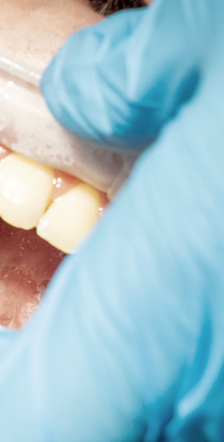

두번째 증상은 잇몸이 붉게 변하며

붓기가 생기는것인데요.

건강한 잇몸은 연분홍색을 띄며,

잇몸에 염증이 발생하면 빨갛게

부워오르게 된다고 했어요.

이러한 경우 잇몸이 예민해져 있어

살짝만 칫솔로 건드려도 출혈이 쉽게

발생하며 통증 또한 느껴질 수 있는

부정적인 상태에 해당됐어요.